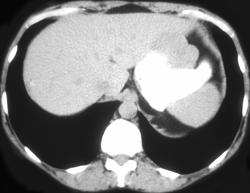

Gastric Leiomyosarcoma (w/ IVC Clot)